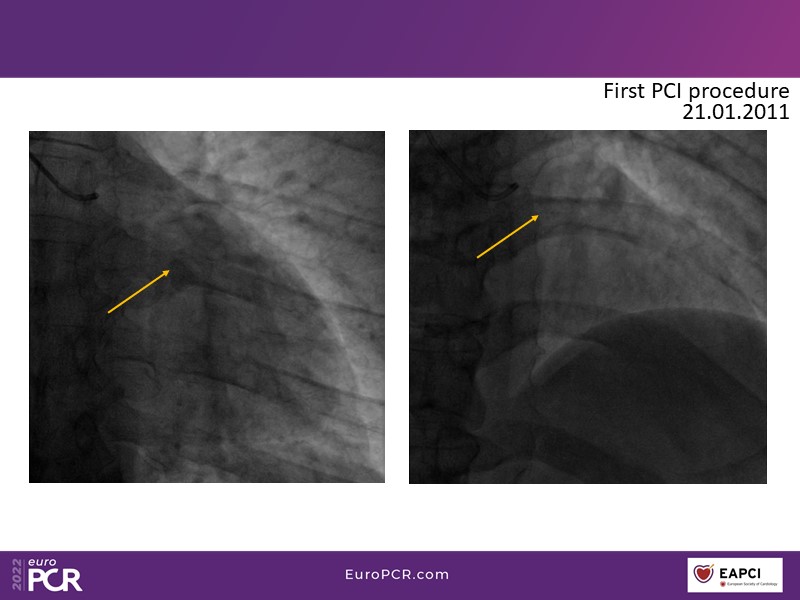

This EuroPCR 2022 session aims to show, based on real-life cases, that even complex coronary disease can be treated without the need for permanent coronary stents. Learn how to prepare the vessel, deliver the therapy, and assess immediate outcomes after "DCB-alone" PCI, discuss de novo, small vessels, and in-stent restenosis cases with follow-up, define what may be an optimal long-term result, refresh the scientific bases, and understand the clinical benefits and safety of paclitaxel DCBs.

- To know how to prepare the vessel, deliver the therapy and evaluate the immediate results after "DCB-alone" PCI

- To discuss de novo, small vessels and in-stent restenosis cases with follow-up and define what may be an optimal long-term result